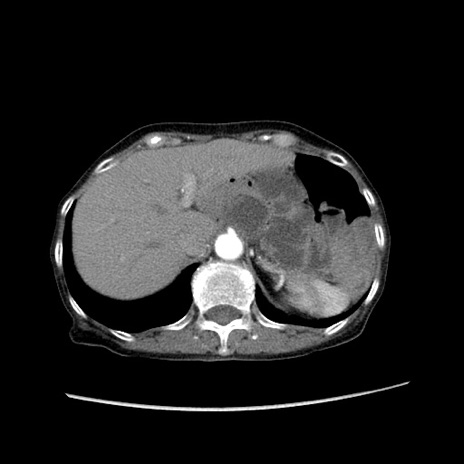

症例25(横断像)

【症例】80歳代女性

【主訴】胸のつかえ感

【現病歴】約9時間前に食後から胸のつかえた感じあり、嘔吐あり、来院。

【既往歴】胃癌(全摘)、胆摘、虫垂炎

【身体所見】心窩部に圧痛あり、反跳痛なし。

【データ】WBC 5700、CRP 0.05